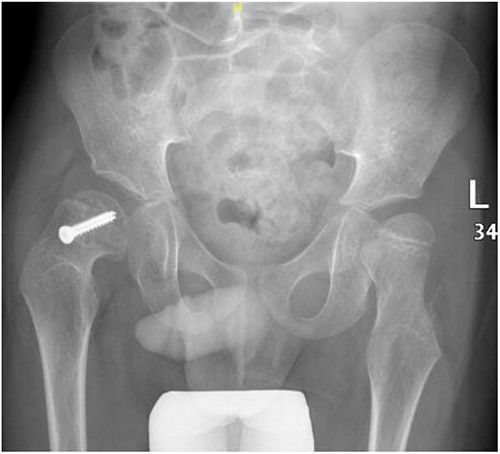

A 5-year-old independent ambulatory Middle Eastern boy with CP who was born preterm and developed grade III intraventricular haemorrhage and periventricular leucomalacia and was on AEDs, including valproic acid (VPA) and levetiracetam (LEV), for >3 years and was controlled over the last year (no history of seizure attack) presented to the emergency room (ER) with right hip pain and inability to bear weight for 4 weeks; the patient had no history of fever or trauma. Physical examination shows a thin, the weight is 12 kg, the height is 101 cm, vital signs within the normal range, tenderness over the right hip, and external rotation of the right hip, with restricted hip mobility. A radiological study was performed ~3 months before the patient presented to the ER for follow-up examination of a left hip coxa valgus deformity with no apparent abnormalities in the right hip (Fig. 1). Initial imaging studies conducted in the ER showed an anterior–posterior view of the pelvic radiograph, revealing Klein’s line [13] not intersecting the capital femoral epiphysis (Fig. 2), and frog-leg lateral view radiograph of the right hip (Fig. 3) confirmed SCFE and Southwick’s slip angle [13] of ~50° (moderate). Laboratory findings were clear for endocrine and renal diseases or infection, except for low vitamin D (total 25-OH Vitamin D: 43.4 nmol/L), suggesting vitamin D insufficiency. The diagnosis was confirmed with clinical and radiological studies as right-sided unstable SCFE requiring surgery. Surgical intervention was performed with percutaneous in situ fixation using a single fully threaded 4.5-mm cannulated screw (Fig. 4). Postsurgical rehabilitation included non-weight-bearing right lower extremities for 6 weeks. Regular follow-up with serial radiology studies showed stable fixation with no migration of screw or further slippage at 6 weeks (Fig. 5) and 3 (Fig. 6), 15 (Fig. 7), and 36 months (Fig. 8). During follow-up, a painless range of motion in the right hip was observed, with full weight-bearing and resumption of his usual activities with no complaints.

Pelvic frog-leg lateral view radiograph showing Southwick’s slip angle 50° in the right hip.